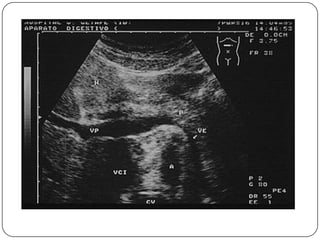

Auxiliares de diagnóstico

 USG

 Imágenes hipoecoicas, encapsuladas y con sombra

acústica, aunque en ocasiones aparecen como

alteraciones inespecíficas de la ecogenicidad, por

lo que resulta difícil diferenciarlas del daño

hepatocelular crónico.

 Sensibilidad (60-80%), Especificidad (45-96%)

 La sensibilidad en el CH alcanza 86%, pero en

lesiones menores de 2 cm es baja.

 Cada 6 meses en pacientes hepatópatas